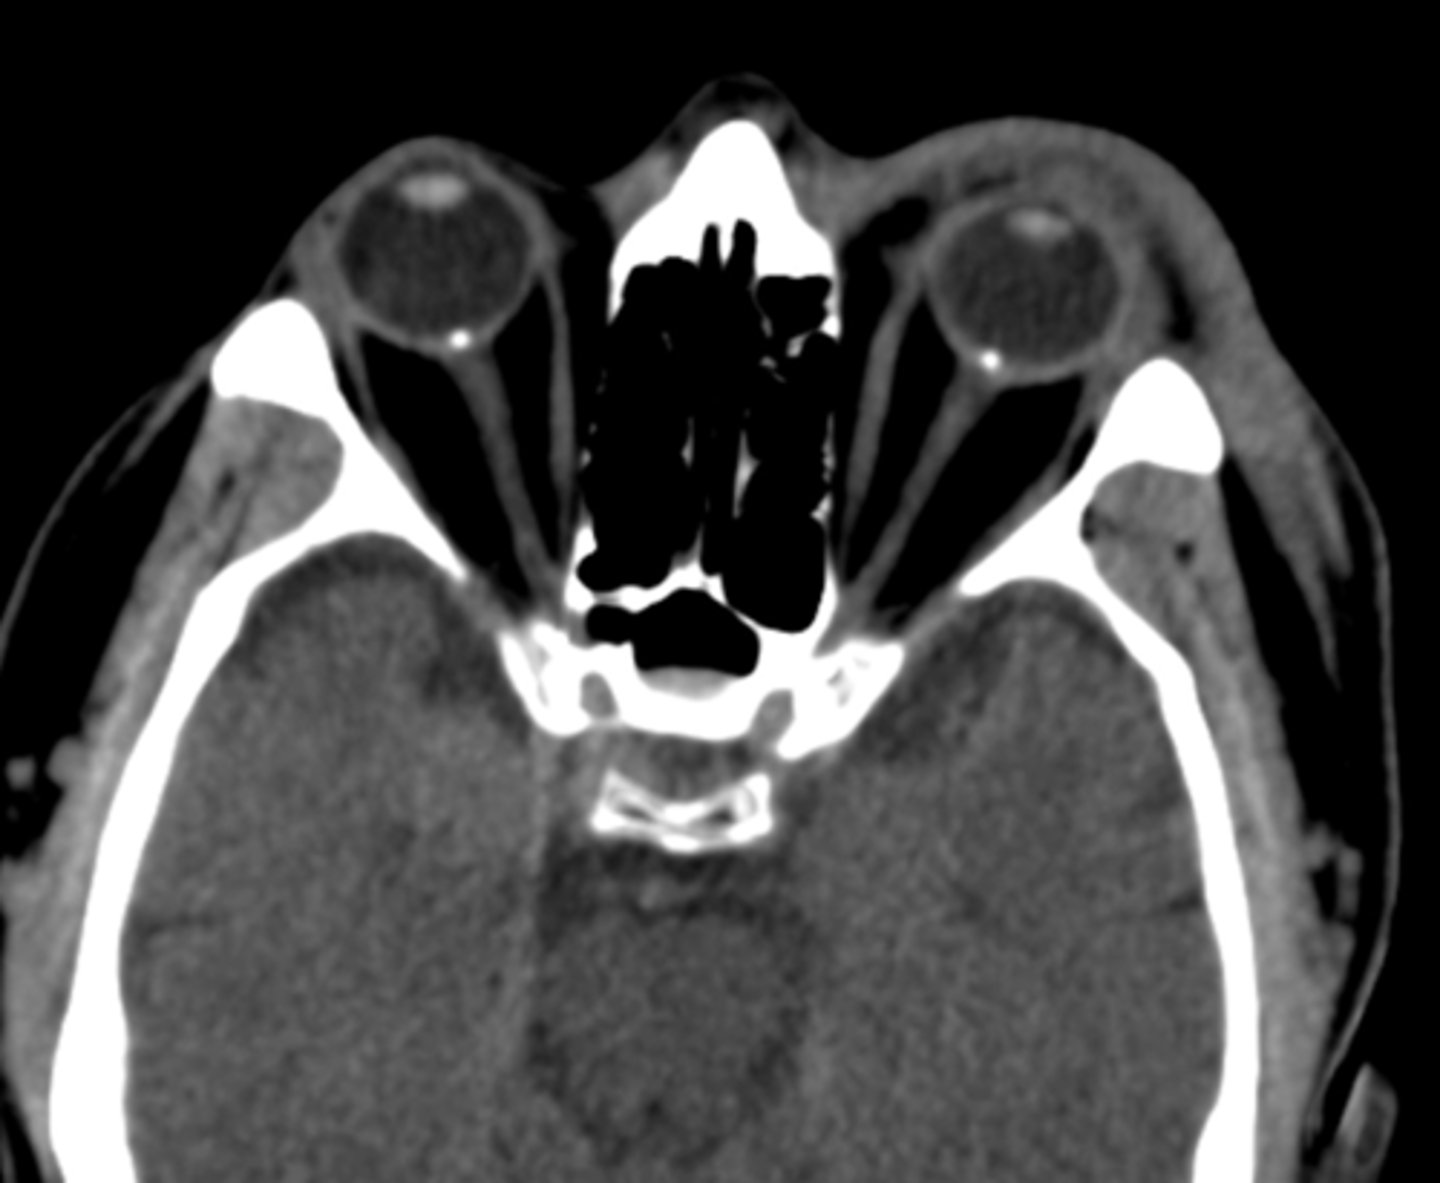

How do disc drusen appear on a CT scan?

hyper-reflective if calcified